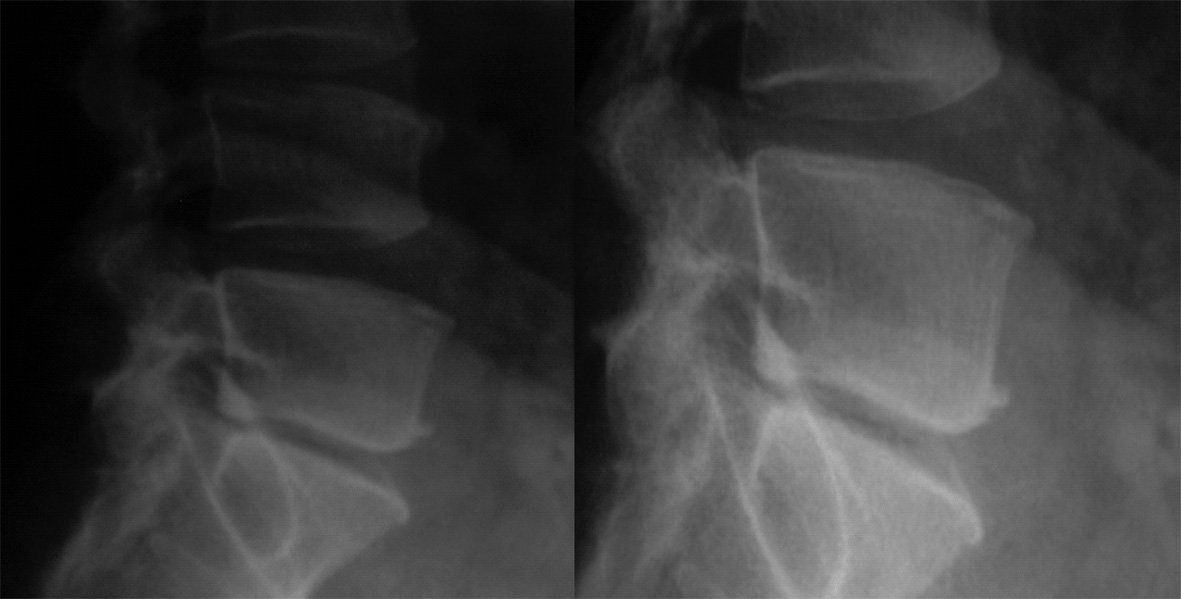

Vous faites des radiographies (clichés ci-dessous). Quel diagnostic vous paraît maintenant le plus vraisemblable ?